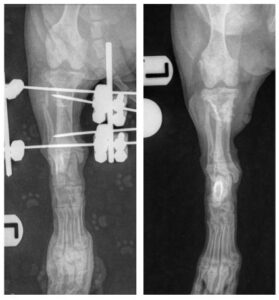

Given how young and tiny Lily was, careful planning was essential. The fracture was repaired using an external fixator – a system of threaded pins placed into the bone and connected externally with rods and clamps to stabilise the fracture.

Because Lily is still growing, it was absolutely imperative that the pins did not interfere with her growth plates. To ensure precise placement, Emma used fluoroscopy (intraoperative radiographs) during surgery.

With Lily’s tibia measuring only 4cm in length, there was very little room for error, accuracy was critical.

Lily’s immediate post-op & 6 week post-op radiographs!

Repeat radiographs confirmed the best possible news – the fracture had healed beautifully allowing us to remove the external fixator.